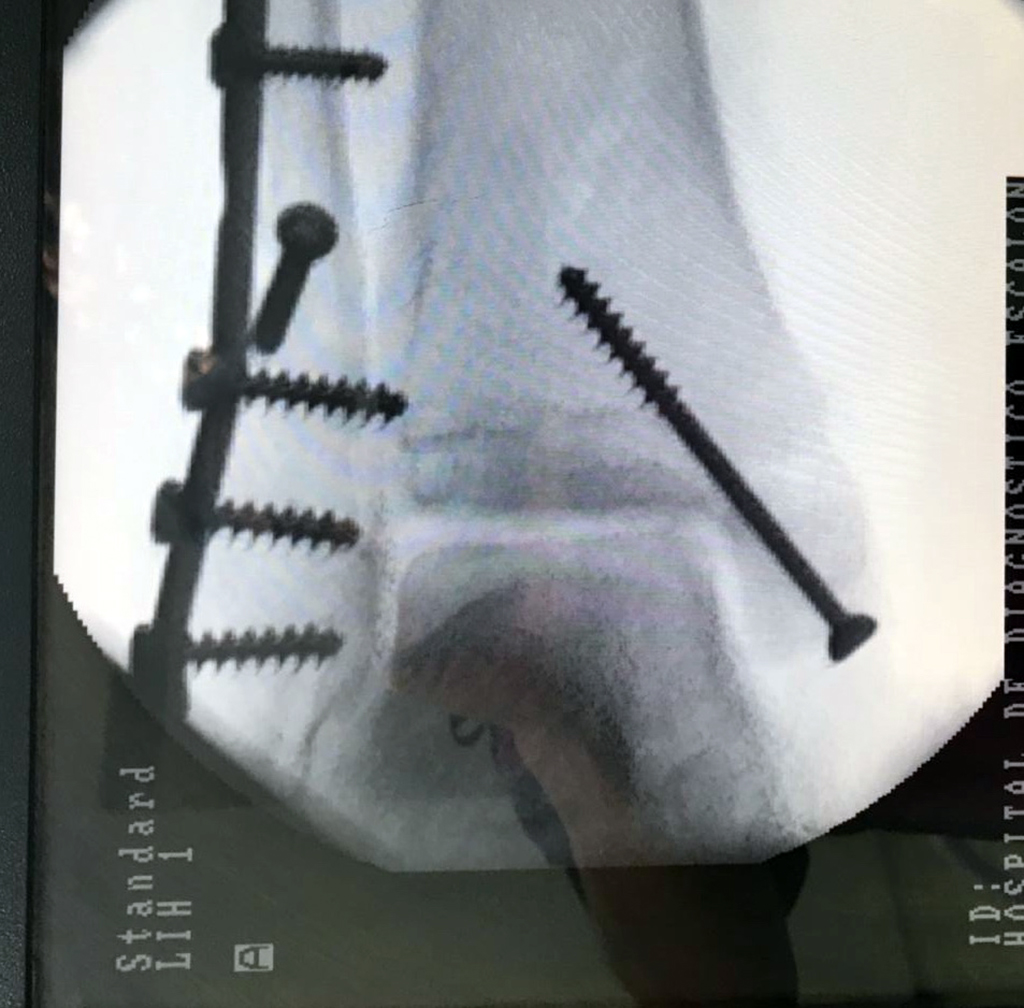

Cuando se necesita cirugía, es probable que esta implique el uso de clavijas de metal, tornillos o placas para sostener los huesos en su lugar mientras la fractura se consolida. Los elementos de soporte pueden ser temporales o permanentes.